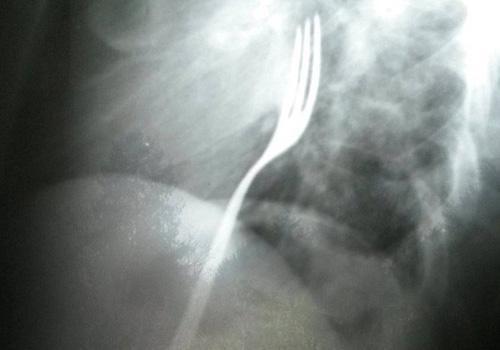

Médicos de Baca esperam que objeto seja expelido naturalmente | Foto: Reprodução

Quando a equipe fez um exame de raio-X no homem, descobriu que o desconforto e a dor eram causados por um garfo preso na garganta de Radu. ?Bebi e apostei com um amigo que conseguiria engolir um garfo sem me machucar?.

Os médicos descartaram uma operação de emergência, e esperam que o garfo saia de forma natural. ?Caso ele chegue ao meu estômago e espete alguma coisa, precisarei ser operado?, explicou o romeno.